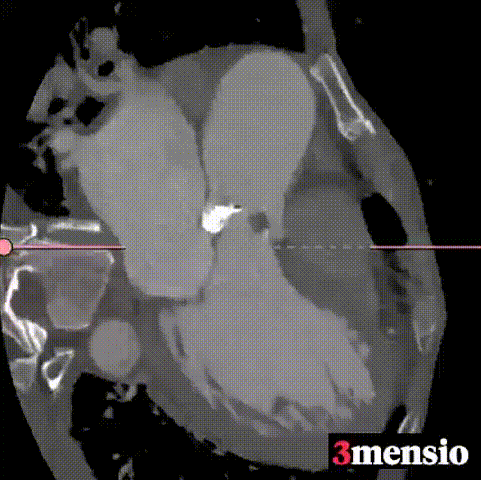

主动脉根部评估及手术策略制定:

1.瓣环周长84.4mm,平均周长径26.9mm;

2.SOV瓦式窦周长114.6mm,平均周长径36.5mm ;

3.LVOT 周长95mm,平均周长径 30.3mm;

4.STJ 周长103.3mm,平均周长径 32.9mm,高度20.4mm。

手术策略制定:

1.CT三维评估表明为Type1二叶式主动脉瓣,左窦与右窦瓣叶融合,无冠窦有重度团块样钙化。

2.左右冠脉开口高度可,且左右瓣叶在高位融合处有明显的增厚,术前经手术团队进行评估,相应冠脉风险较低。

3.拟采用22mm球囊进行预扩,植入TaurusElite AV26瓣膜,使用Cusp-Overlapping技术零位或高危释放的策略降低术后新发传导阻滞风险。